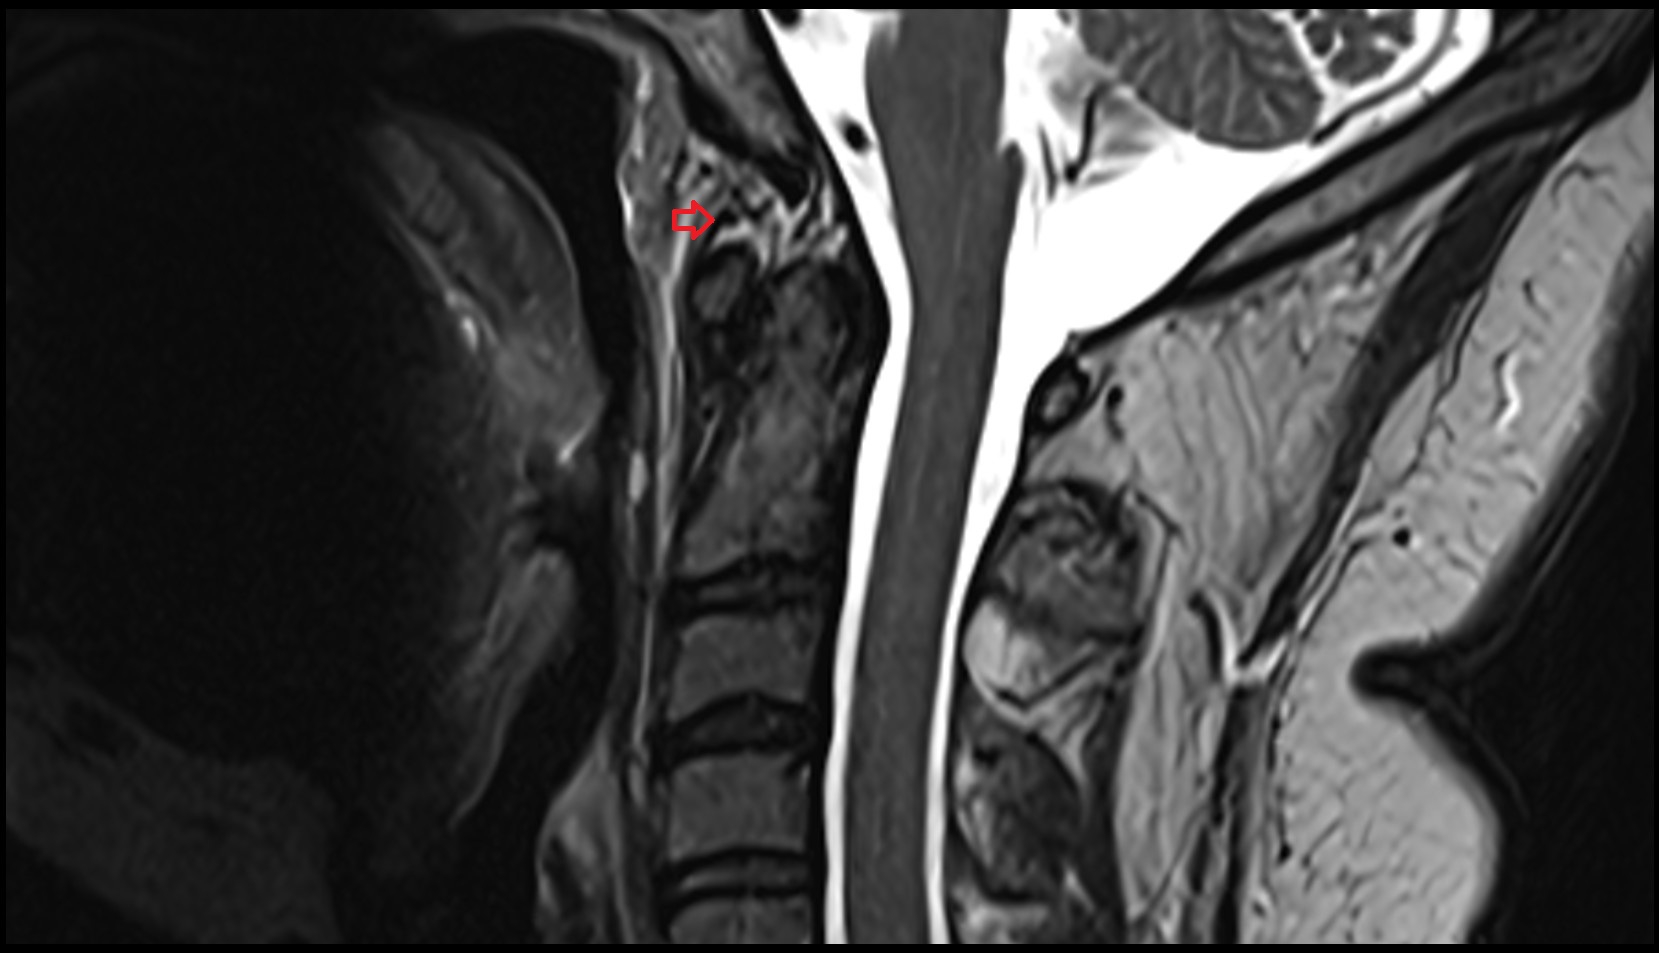

- Spinal cord

- Upper cervical spinal cord

- Body of vertebra